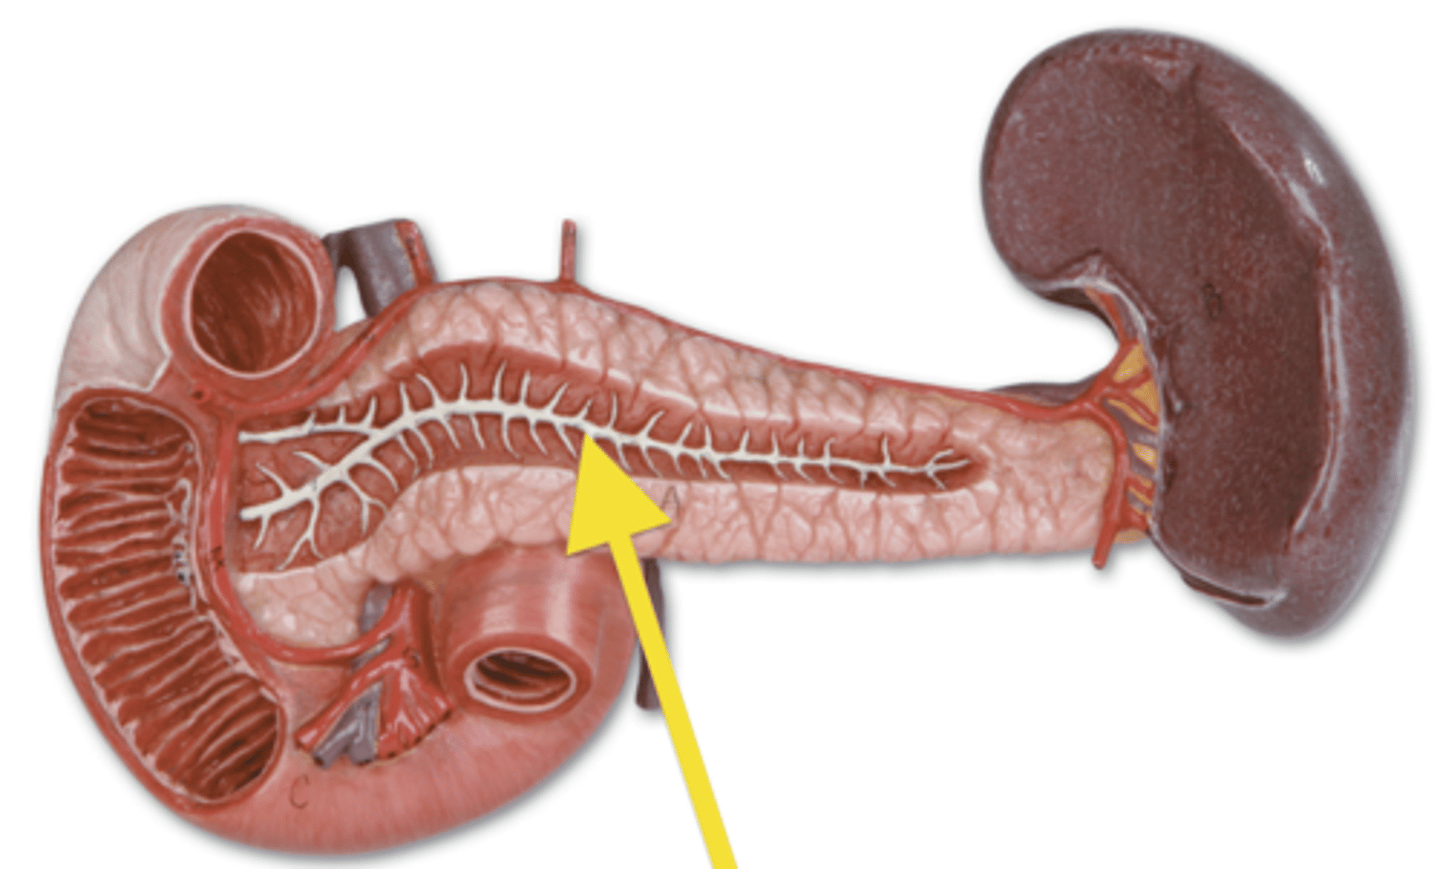

pancreas

organ

spleen